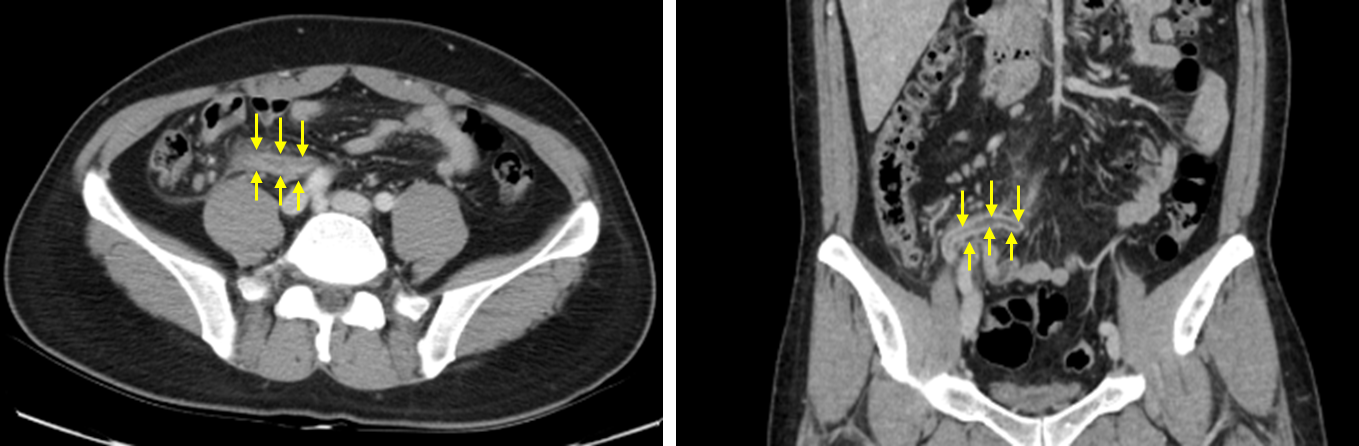

40세 남자가 2일 전부터 오른쪽 아랫배가 아프다며 응급실에 왔다. 2일 전에는 윗배에 불편한 느낌이 있다가 점차 오른쪽 아랫배의 날카로운 통증으로 변하였다고 한다. 혈압 126/96 mmHg, 맥박 100회/분, 호흡 20회/분, 체온 38.2℃이다. 오른쪽 아랫배에 압통과 반동압통이 있다. 혈액검사 결과는 다음과 같다. 복부 컴퓨터단층촬영 사진이다. 가능성이 큰 진단명을 고르시오. (한 가지)

Img | CT: Appendiceal wall thickening & inflammation near appendix |

• 확실한 감별을 위해 촬영한 CT상 appendix 근처의 지저분한 inflammation이 관찰되고, appendix와 그 wall이 전반적으로 두꺼워져 있음이 관찰된다. 이는 급성 충수돌기염에 부합하는 소견이다.